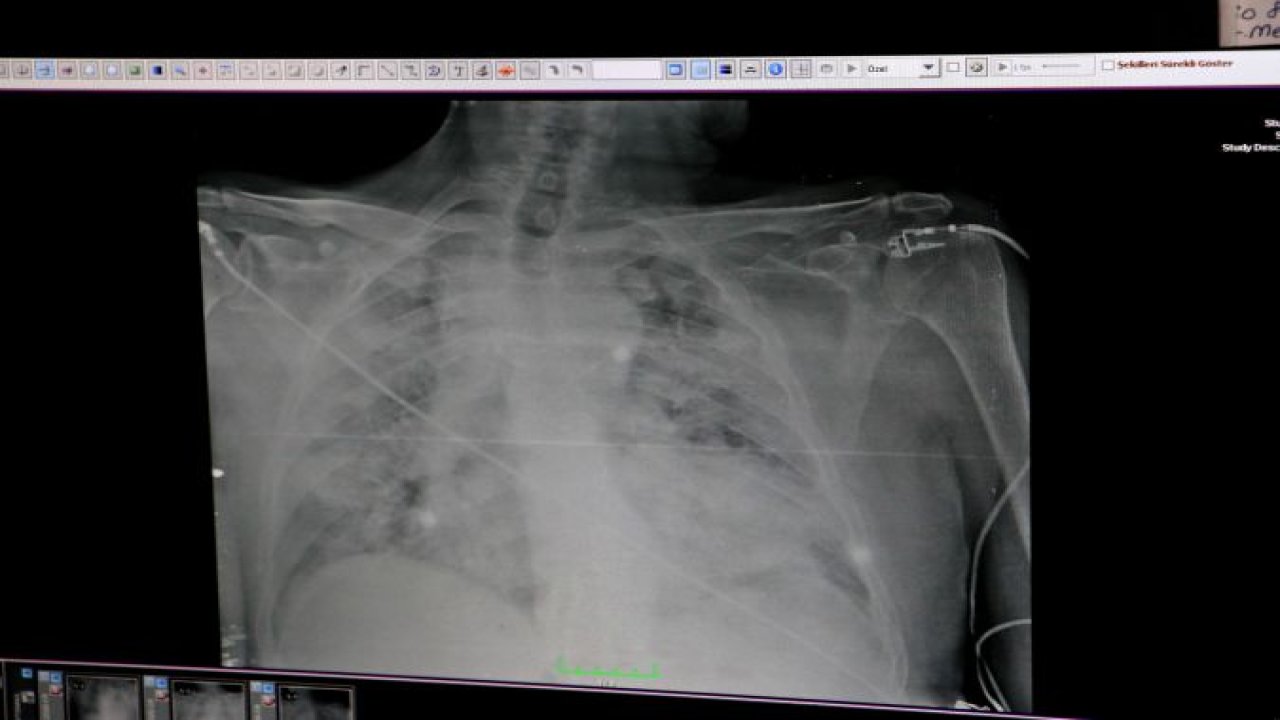

89 yaşında korona virüsü ve kalp krizini yendi